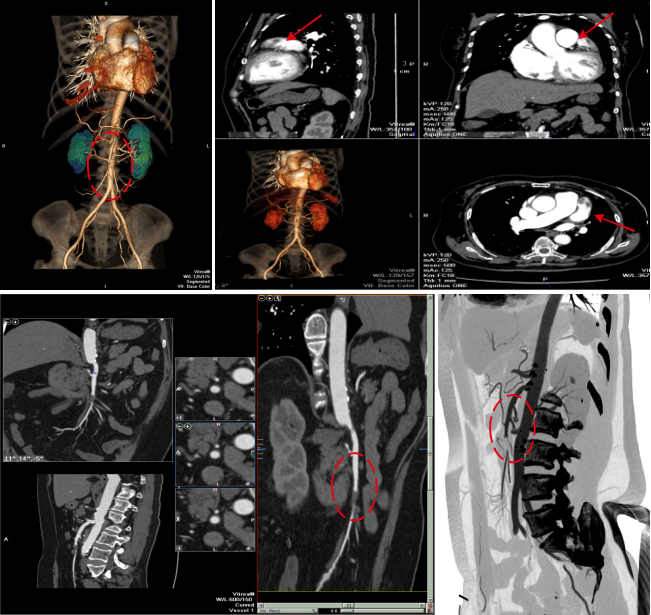

病例二 男,52歲, 以“ 下腹部包塊3天” 門診就診。 查體: 臍周可觸及包塊, 無(wú)壓痛。術(shù)后病理結(jié)果: 腸系膜內(nèi)胃腸道外的GIST, 高分化。

平掃期 動(dòng)脈期 門脈期 延遲期

該檢查使用最新的AIDR-3D迭代重建技術(shù),最大程度的降低了掃描的輻射劑量,并且能夠得到高清的圖像質(zhì)量。此病人術(shù)前4期檢查加上術(shù)后復(fù)查多次掃描總劑量?jī)H5mSV左右,目前,此技術(shù)可以用在全身各部位的檢查。

病例一 34歲, 男, 右肝血管瘤。

灌注檢查可見(jiàn)肝臟內(nèi)一類圓形病灶,AF為血流高灌注,PF為血流低灌注。

可以自動(dòng)一鍵提取肝動(dòng)脈、 門靜脈以及腫瘤, 并且進(jìn)行融合, 觀察腫瘤與動(dòng)脈及門脈血管的關(guān)系。

640層寬體探測(cè)器CT對(duì)于肝臟全器官灌注掃描,不但能夠精確顯示動(dòng)脈期、門脈期、靜脈期的3D解剖結(jié)構(gòu),而且可以同時(shí)探查腫瘤的供血?jiǎng)用}、流出靜脈,分析肝實(shí)質(zhì)的血供和灌注情況。所有這些檢查都以極低的劑量在一次檢查中完成,對(duì)肝腫瘤的診斷與治療及效果評(píng)估具有重大意義。除此之外,特有的肝血管融合技術(shù),可用于肝臟手術(shù)模擬以及肝臟腫瘤的分割和量化。